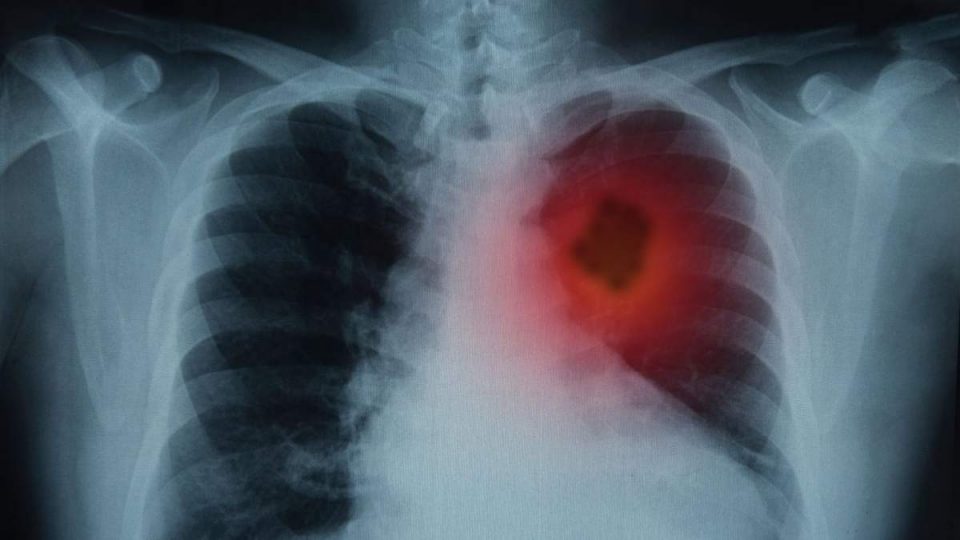

Рак легень – це один із найтяжчих та найпоширеніших видів онкологічних захворювань. Він займає особливе місце серед причин смертності внаслідок ракових захворювань у всьому світі. Щорічно в Україні реєструється понад 13 тисяч нових випадків раку легень, з яких значна частина виявляється на пізніх стадіях, коли лікування вже не може стати ефективним. Основні причини раку легень включають куріння, забруднене повітря та вплив канцерогенів. Це призводить до численних запитань про шляхи, методи та заключні етапи розвитку захворювання.

Розвиток раку легень зазвичай відбувається через кілька послідовних етапів. На початку захворювання клітини легень підлягають мутаціям через вплив навколишніх факторів, таких як куріння тютюну. З часом мутації накопичуються, що призводить до формування злоякісної пухлини. На ранніх стадіях рак може не виявлятися жодними симптомами, що ускладнює діагностику. Після цього хвороба починає прогресувати, викликаючи біль, задишку та інші фізичні розлади.

На різних стадіях раку легень можуть з’явитися різноманітні симптоми. У пацієнтів часто спостерігаються тривалі кашель, біль у грудній клітці та респіраторні інфекції. Виникають також системні симптоми, зокрема, втрата апетиту, надмірна втома та паління в грудях. Залежно від стадії розвитку, коли рак стає більш поширеним, з’являються метастази, які впливають на інші органи, ускладнюючи загальний стан пацієнта.

Особливі метастатичні ураження можуть включати поширення в печінку, кістки або головний мозок. Коли пухлина досягає 4 стадії, медикам часто доводиться боротися не лише з основним захворюванням, але й з його ускладненнями, такими як гостра дихальна недостатність, інфекції та зниження загального стану здоров’я. Кожен етап розвитку раку легень потребує індивідуального підходу до лікування і паліативної допомоги.